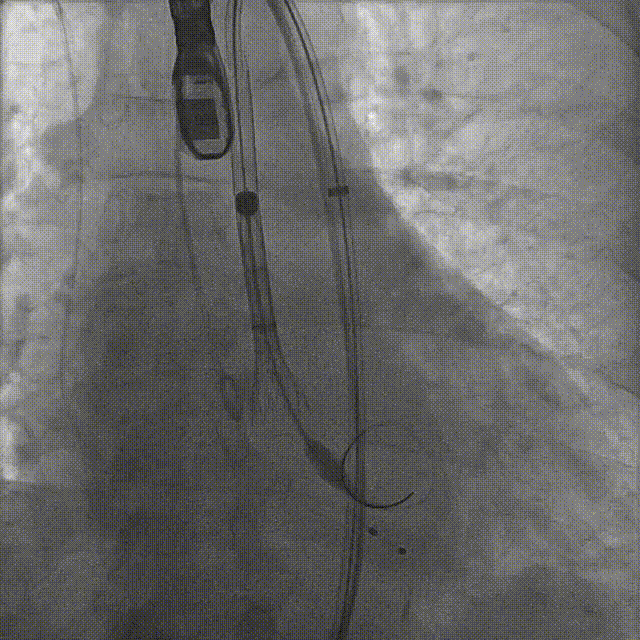

患者病史 体检发现心脏瓣膜病半月余,平素无症状 ,有高血压病史。 后来院复查诊断为:主动脉瓣狭窄(重度)、先天性主动脉瓣二叶瓣畸形、心室肥厚、升主动脉扩张心功能 I 级(NYHA 分级)、高血压病 2 级(极高危)。 术前 CT:Type0型二叶瓣,瓣叶增厚,无钙化,类风湿性;瓣环径25.6mm,LVOT稍收窄,瓣环水平夹角66.6°,轻微横位心;左右冠开口高度可,瓣叶不长,无冠脉风险;心室收缩末内径约32mm,室壁增厚;外周入路无明显迂曲,无钙化、双侧内径可、双股中分叉,右侧为主入路能够支持20F大鞘通过。 造影角度及入路:LAO 6° CAU 13° 手术策略 采用右侧股动脉为主入路,左侧为辅助入路,常规穿刺。推荐使用20球囊预扩,预装TAV29瓣膜,初始定位对齐瓣环上0mm开始释放。 手术过程 20号球囊预扩无明显腰征 输送器过弓跨瓣顺滑 80%工作位观察 术后造影,瓣膜释放位置良好,无瓣周漏 术后超声:人工生物瓣释放后形态满意,瓣叶开放、关闭活动良好,无瓣周漏;跨瓣血流速度降至 2.5m/s,平均压力梯度6mmHg,符合手术预期。 Prostyle A®预装干瓣——“刚柔并济”助力临床最优化解决方案: 丝滑过弓能力:Prostyle A®短瓣架设计联合远端超滑亲水涂层,即使没有联合使用snare,都可以柔顺过弓,该例横位心的患者更好的展现了输送系统的柔顺性; 平衡的径向支撑力:该例患者Type0型二叶瓣,术后形态展开良好且无瓣周漏,在横位心等复杂情况下实现稳定锚定。 80%可回收设计:80%工作位观察,起搏时间更短,对患者损伤减少到最小,也利于术中精准调整瓣膜位置,保证术后效果。